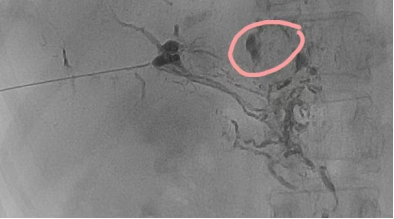

史先生胃癌根治术后第3天腹腔引流液增多,平均每天约800ml,保守治疗2周效果欠佳。考虑术后肝门部淋巴漏可能。于东院肿瘤外科就诊,在介入手术室曾如雪护士长协调及李志恒老师配合下,超声医学科台明辉主任超声引导下细针定位肝门部,汤瑞祥主治医师细针穿刺成功肝门部淋巴管后注入造影剂,显示淋巴管漏点位置,缓慢注射生物胶。术后患者很快引流液量降低至正常范围并顺利拔除引流管。治疗后1周复查CT未见明显腹腔积液。